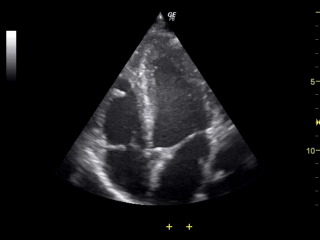

If excess fluid accumulates within this space, it is called a pericardial effusion. The danger of this effusion depends on two things:

- A transthoracic echocardiogram, to see the amount of fluid and look to see if the heart is being compressed